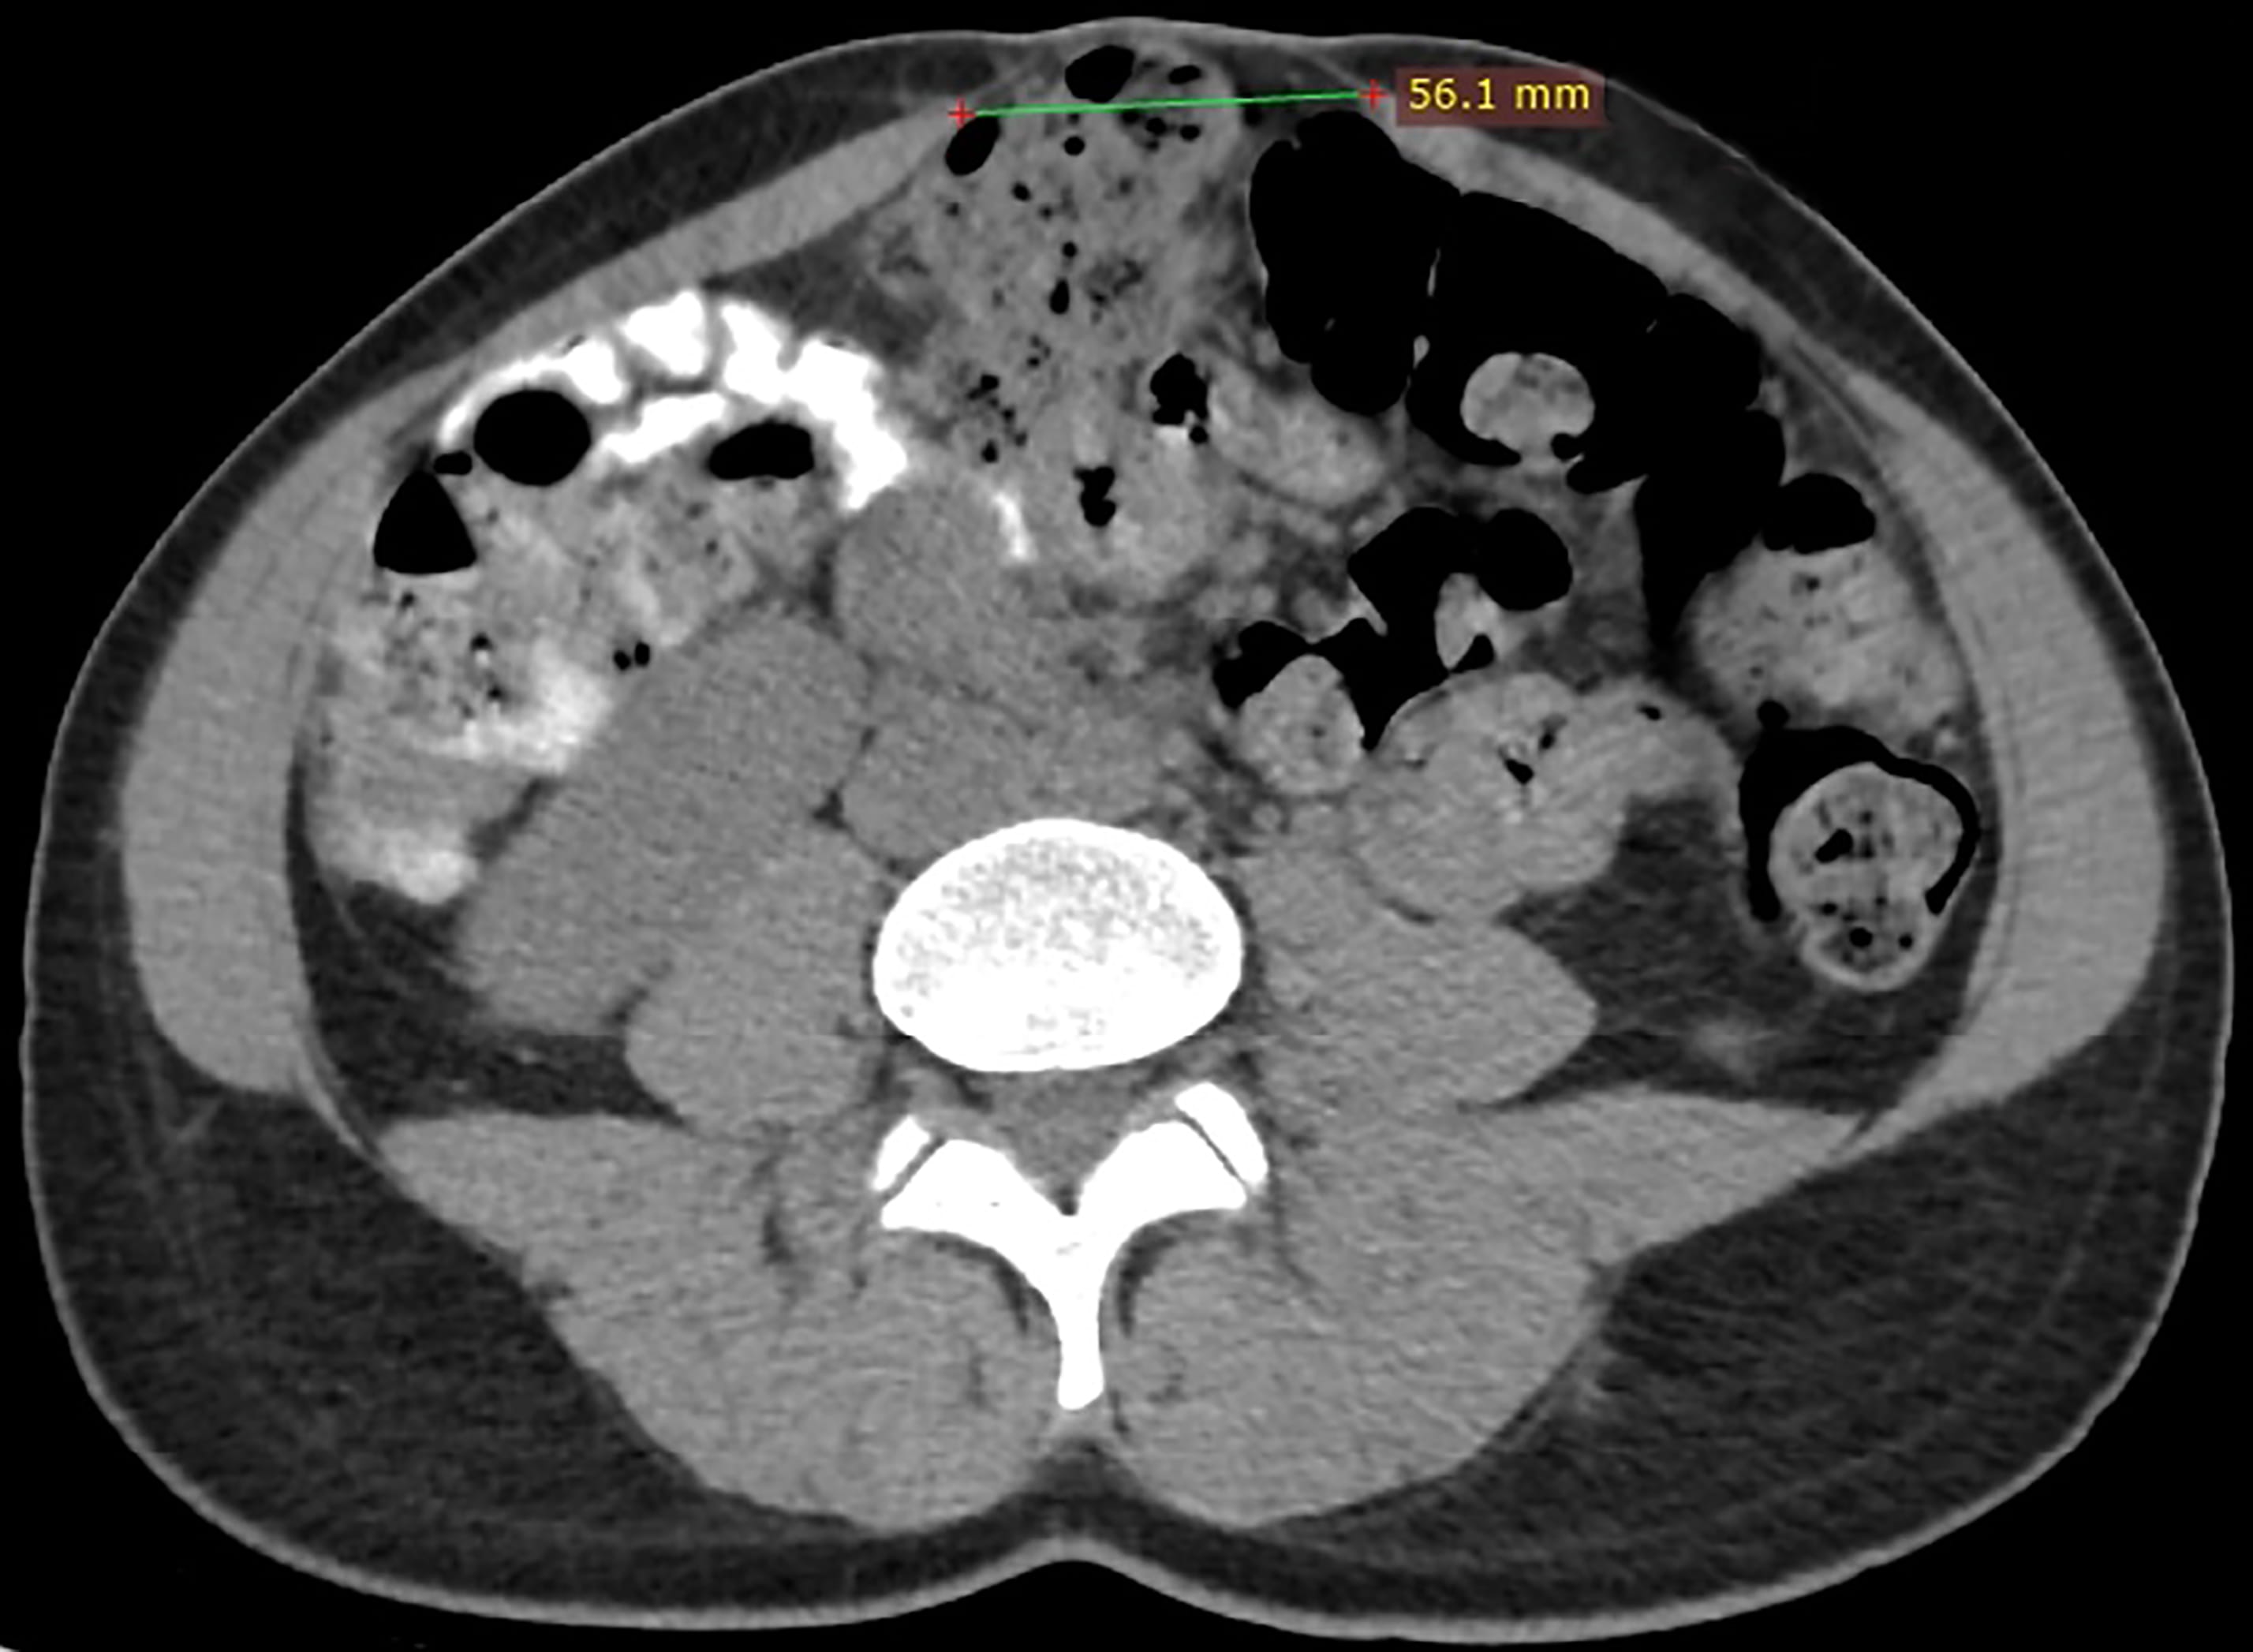

To diagnose the presence of DRA and its severity the interrecti distance (IRD) is measured [4]. Palpation, caliper, ultrasound (Fig. 3), CT (Fig. 4) and MR are used to measure IRD [2, 4]. To date there is no consensus which method should be applied. Swedish national guidelines recommend diagnosis using caliper or ruler for measurement. Ultrasound or other imaging modality is recommended when concomitant hernia is suspected [7]. Corvino et al. [17] promote the use of dynamic ultrasound in case of suspected hernia. They point that computed tomography is a static examination, while dynamic ultrasound could demonstrate the movement of abdominal contents [17]. The finger-width method is widely used, as it is economical and relatively convenient [2]. However, ultrasound, CT or MR to measure IRD are more accurate and may exclude any concurrent ventral hernia [2, 6].

Fig. 4.Interrecti distance (IRD) measured by computed tomography: IRD 56 mm.